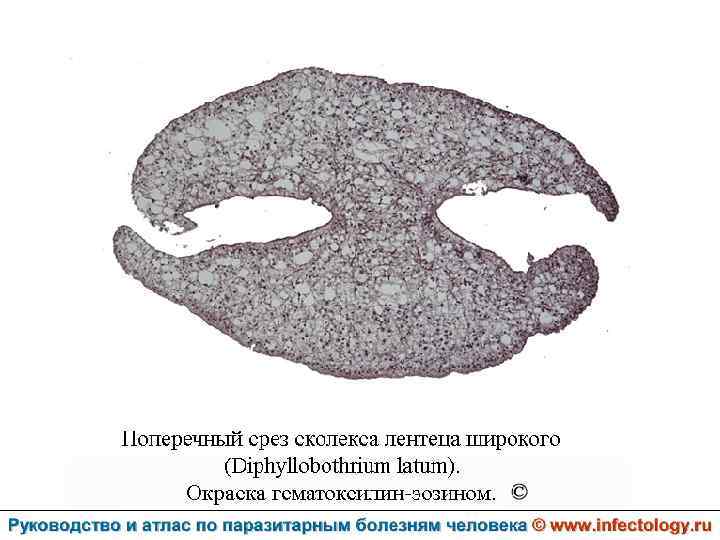

Дифиллоботриоз (шифр по МКБ 10 – B 70. 0) – зоонозный биогельминтоз с хроническим течением, характеризующийся нарушением функций верхнего отдела пищеварительного тракта, а при тяжелом течении - развитием анемии.